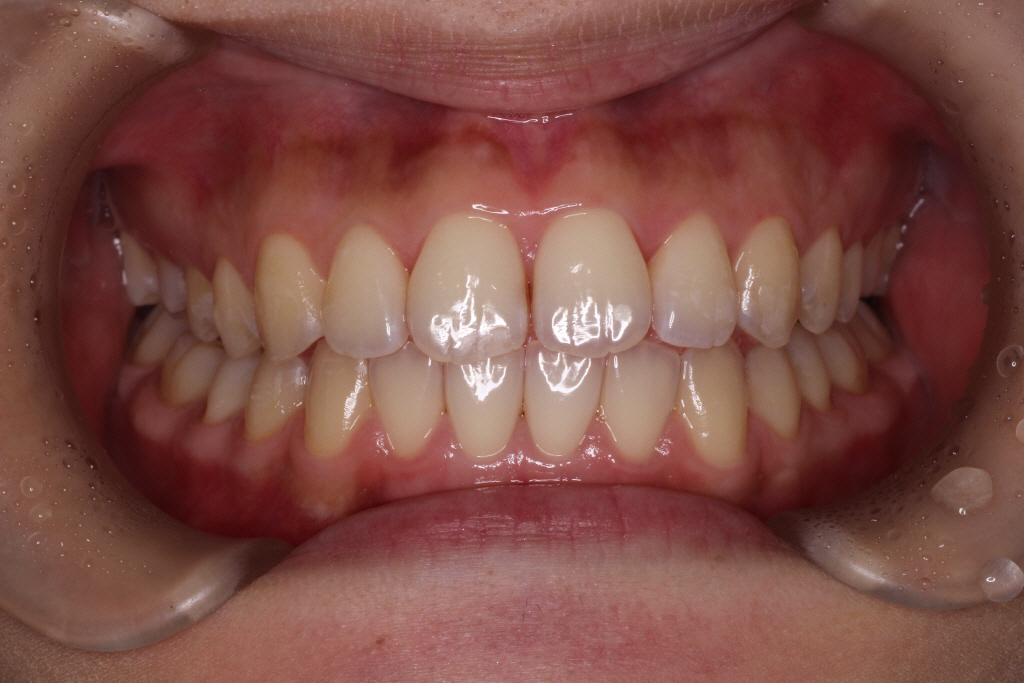

下が1回目のインビザラインが終わった時の写真です。気になっていた前歯のねじれはきれいに並びました。